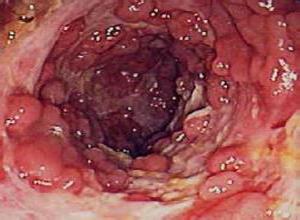

简介小肠腺瘤是发生于小肠黏膜上皮或肠腺体上皮的良性肿瘤,好发于十二指肠和回肠,体积小、带蒂,呈息肉样生长,是一组由纤维血管为核心覆盖黏膜和黏膜下层的息肉样突出物所构成,故又称肠息肉。